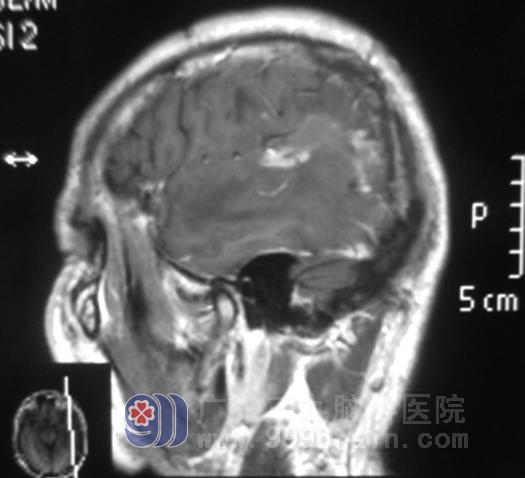

全麻下行“左侧颞叶占位切除+去骨瓣减压术”,病灶基本全切。第二天文哥清醒,回答切题,语言流利。病理报告:(左侧颞顶叶)脑组织呈广泛性坏死、出血,伴胶质细胞增生及慢性炎症反应。术后MRI示病变组织基本全切,水肿较前明显消退;复查MR发现炎性组织以及水肿已基本消失。